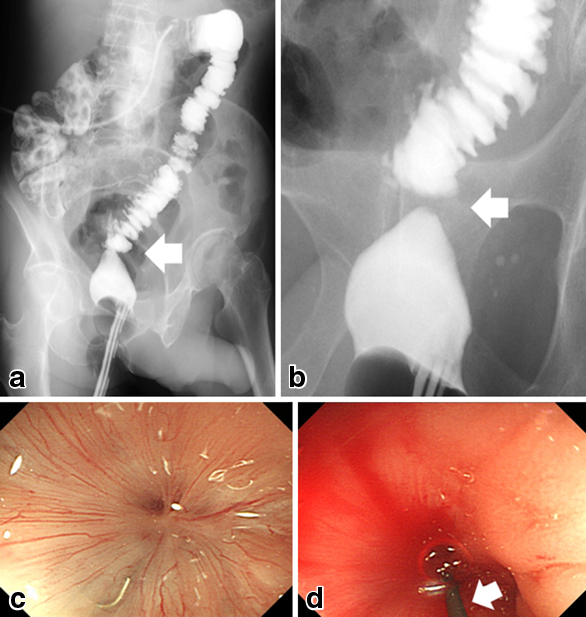

Study before Yamanouchi method. a, b) Simultaneous contrast enema study from the stoma and anus showed the complete occlusion of rectal anastomosis. On transanal contrast, only the shortened rectum was contrasted. The obstruction was shown by contrasting with the transanus/stoma. The white arrows show the occlusion. c) A complete occlusion was confirmed by colonoscopy from the stoma side. d) There was also no opening from the anal side and no clearance through which the guide wire passes. The white arrow shows the guide wire (35's radial focus).

既往歴:高血圧,高脂血症

現病歴:2011年1月,S状結腸と直腸Rbの重複癌に対し,腹腔鏡下低位前方切除術を施行した.術後,縫合不全による腹膜炎と腹腔内膿瘍を来したため,横行結腸に人工肛門を造設した.ドレナージと抗生剤投与による保存的治療で縫合不全による膿瘍は軽快したが,術後3か月の後に人工肛門の閉鎖を目的として行った注腸検査で吻合部に閉塞が指摘された.大腸内視鏡で肛門と人工肛門の両側から閉塞部を観察すると,閉塞区間は約5 mm程度ではあったが,わずかな開通部もないことが確かめられた(Fig. 1).このため内視鏡的切開や外科的手術(閉塞部切除/再吻合),磁石圧迫吻合法を考慮した.しかしながら,術後経過観察のCTで右肺上葉に結核病変を指摘されたため,約2年の結核治療後に人工肛門閉鎖および,腸管吻合部閉塞解除を試みることになった.